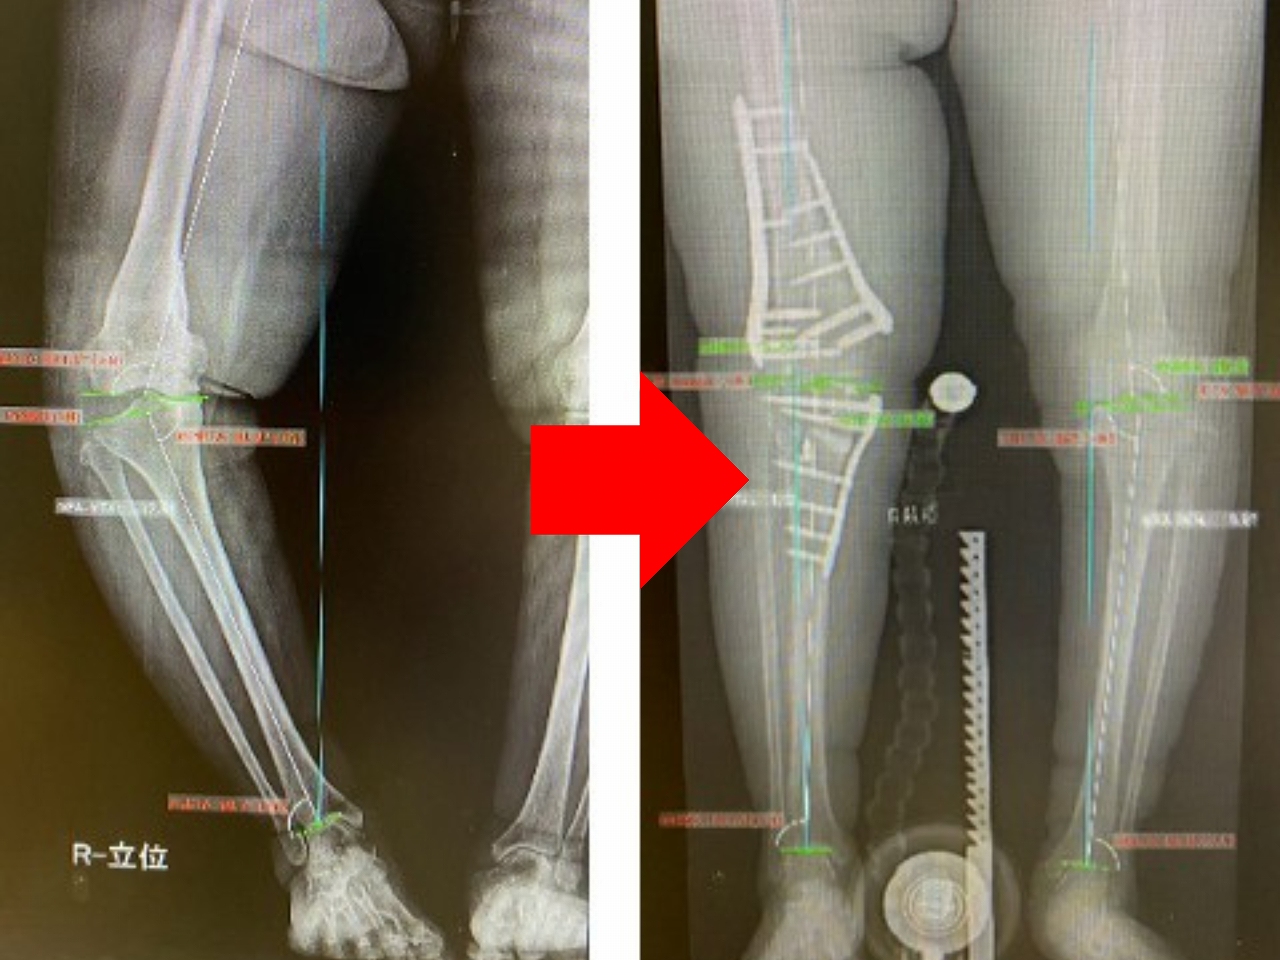

手術前と手術後のレントゲン

骨切り術は、軟骨のすり減りや変形が膝関節の内側だけ、もしくは外側だけに限局している場合に適応となります。特に多いのは、すり減りが内側に大きくO脚になっている人です。

骨切り術にはいくつか種類があり、これまで一般的に行われてきたのは、「高位脛骨骨切り術(HTO)」といって、脛骨(すねの骨)の上の方を切って角度を矯正する方法です。

最近は、より患者さんの状態に合わせた骨切り術が行われるようになってきました。例えば、脛骨の内側から外側に向かって骨を切り、内側を開いて矯正する「内側開大式高位脛骨骨切り術(OWHTO)」、脛骨と大腿骨(太ももの骨)の両方の骨切りを同時に行い、できる限り正常な状態へと改善する「ダブルレベルオステオトミー(DLO)」、膝蓋骨の位置を保つことで術後の軟骨損傷の発症リスクを減らす内側開大式脛骨粗面下骨切り術(DTO)などがあります。

…このように、新しい骨切り術の方式が開発されていることによって、これまでは、人工膝関節しか選択肢がなかった人が骨切り術で治療を受けられ、自分の膝を残しながら元の生活に戻ることも可能です。